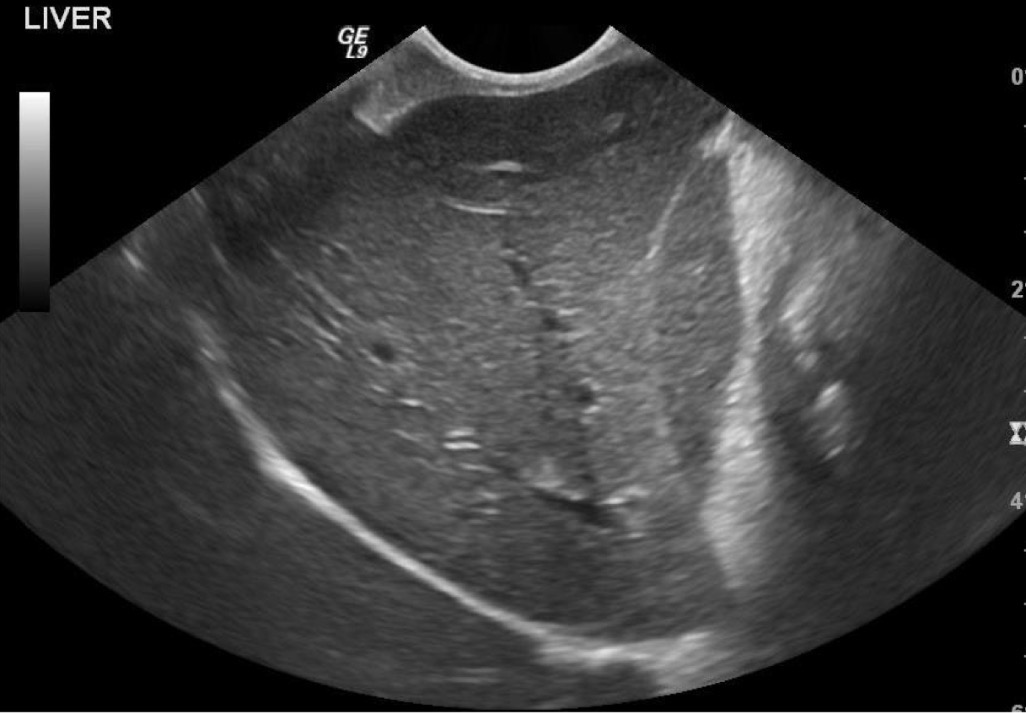

Liver

What organ is most prominent in this ultrasound?